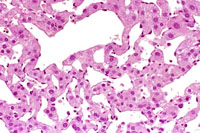

This hemangioma has isolated small clusters of hepatocytes; higher magnification shows proliferation of flattened endothelial cells.